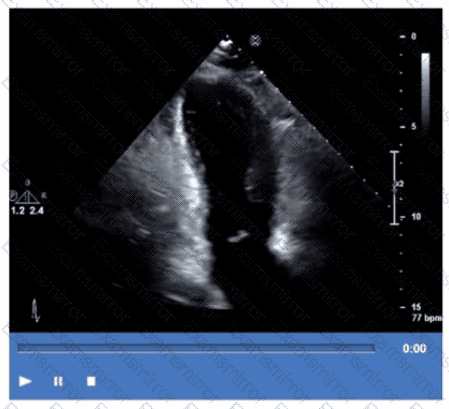

Which finding is best demonstrated in this video?

Which coronary artery territory is associated with the wall motion abnormality demonstrated in this video?